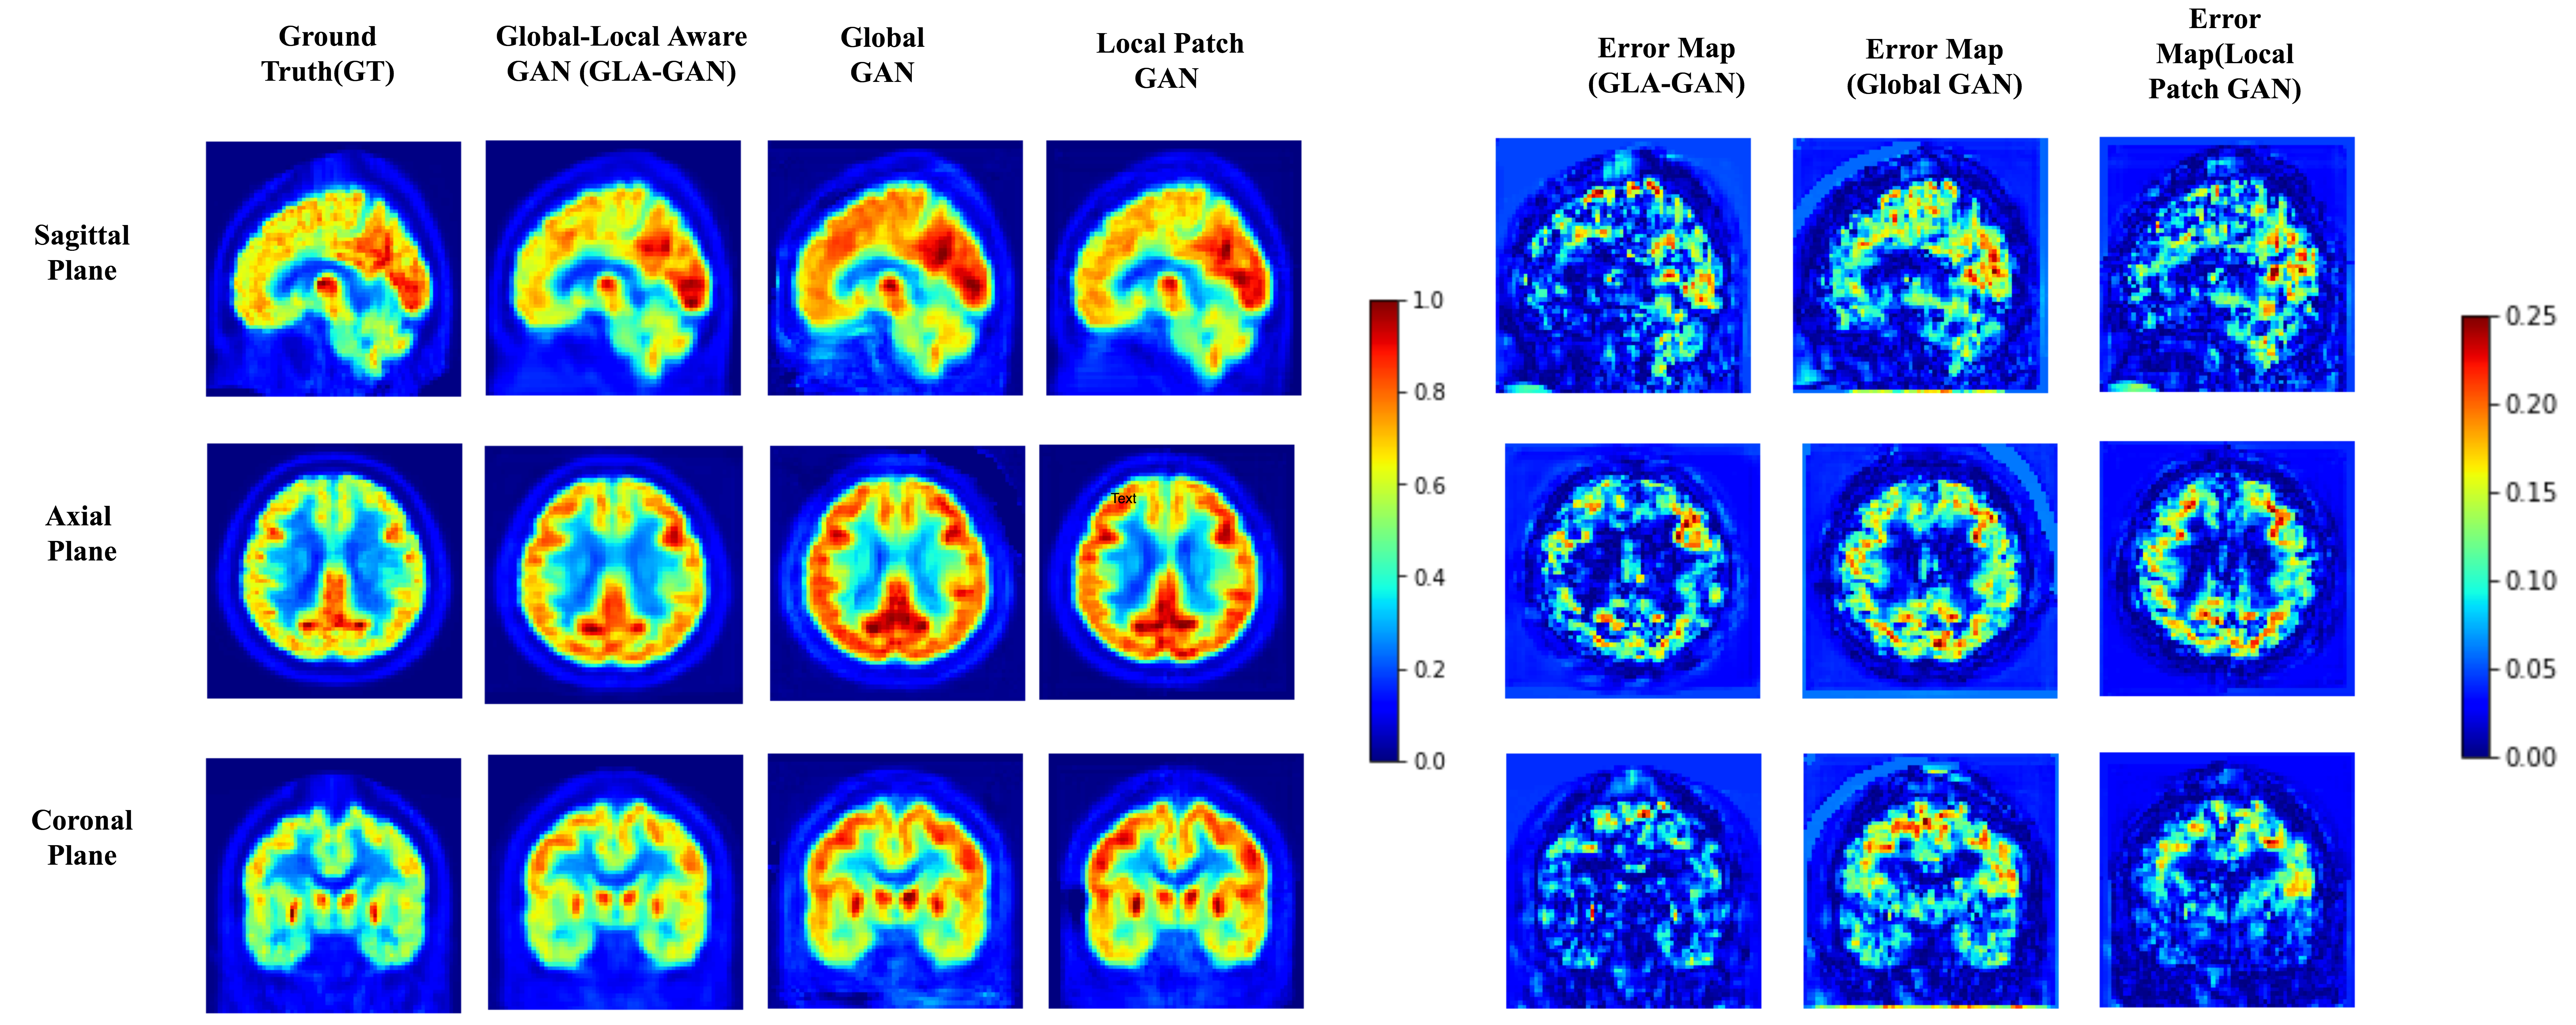

Refer to caption

Figure 2: (a)

Figure 3: (b)

Figure 4: Qualitative comparison of PET scans synthesized using GLA-GAN, Global-GAN and patch based Local-GAN. Ground truth and estimated PET scan along with error maps corresponding to each of the models is presented for an AD (a) and CN (b) sample in axial, coronal and sagittal views. [Best viewed in color]

Firstly, we demonstrate the significance of incorporating both global and local contextual information simultaneously through parallel modules in the GLA-GAN framework. To this end, we compare three variants of the multi-path architecture: (i) Global GAN, (ii) Local GAN and (iii) Global-Local GAN. Figures 4 (a) and (b) show qualitative visualizations of PET scans synthesized using these three models along three planes (axial, sagittal and coronal) for an AD and CN sample respectively. In addition to the generated images, error maps with respect to the ground truth are also presented. Although not readily apparent, there are subtle differences in the estimates generated by the individual Global and Local only modules. A closer observation reveals that while the local module is better at capturing intricate details like the shape of ventricles, the global module achieves better estimate of the FDG uptake intensity. However, it is clearly evident from both synthesized images and error maps that the hybrid model predicts the FDG uptake patterns for both classes of samples (AD and CN) most accurately.